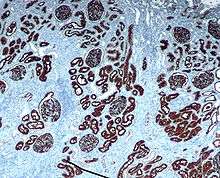

Kidney- Microscopic cross section of the renal cortex

CD10 immunohistochemical staining of normal kidney. CD10 stains the proximal convoluted tubules and glomeruli.- Renal cortex